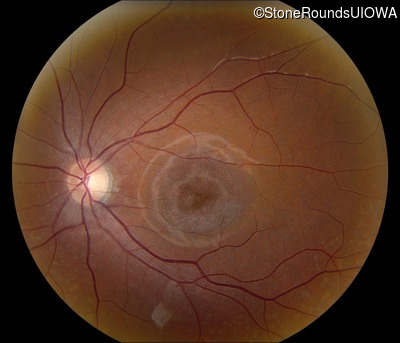

AR Stargardt Disease (IIA)

AR Stargardt Disease (IIA)

| Age at visit: 12 years |

| Age at visit: 13 years |

| Age at visit: 15 years |